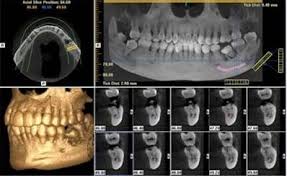

Without socket preservation, the bone quickly resorbs resulting in 30–60% loss in bone volume in the six months after dental extraction. The jaw bone will never revert to its original shape once bone is lost and tissue contour has changed.

The placement of an implant at a site with a thin crestal ridge (e.g., postextraction ridge) could result in a significant buccal dehiscence. Thus, it seems prudent to prevent alveolar ridge destruction and make efforts to preserve it during extraction procedures.

However, it is possible to minimize such problems by simply carrying out ridge preservation procedures in extraction sockets using grafting materials with or without barrier membranes. Socket preservation procedures help reduce horizontal or vertical alterations in the alveolar ridge near the site of a tooth extraction.